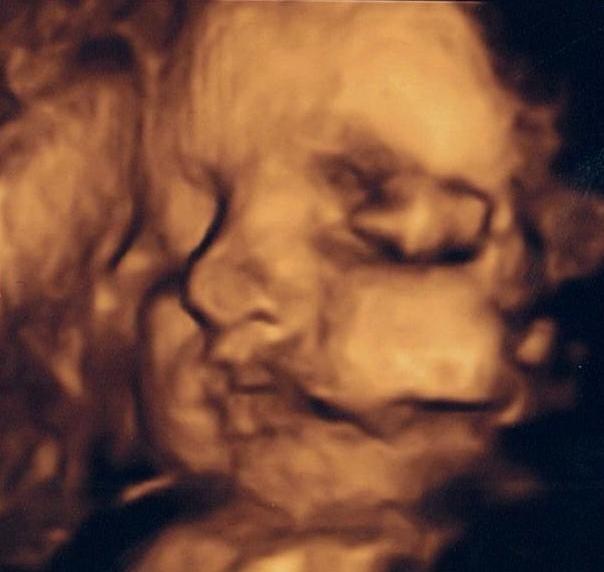

Så har vi for anden gang været til 3D scanning - en gratis én af slagsen fordi første forsøg mislykkedes totalt. Vores 'Mini' gemte sig fuldstændig væk, lagde sig med hænderne op foran ansigtet og videre lå navlesnoren ind foran ansigtet og lavede nogle grimme skygger på billderne, så det ser ud som om lillefis har et blåt øje

Vi havde egentligt besluttet ikke at få lavet en 3D scanning (da jeg synes det er lidt for dyrt og poppet), men min kæreste havde alligevel bestilt tid som en overraskelse til mig, hvilket jeg naturligvis blev super glad for. Nu føles det bare en lille smule tamt, da vi på de to forsøg stadig ikke har fået de billeder, som vi gerne ville have haft, MEN uanset var det dejligt at se den lille pige igen, se hende smile, spytte vand, række tunge og bevæge sig vildt og voldsomt rundt

Selvom billederne er ret dårlige er der flere af vores venner + familie, der har kommenteret, at de tydeligt kan se nogle af mine ansigtstræk hos hende, det går lige i

på mig.